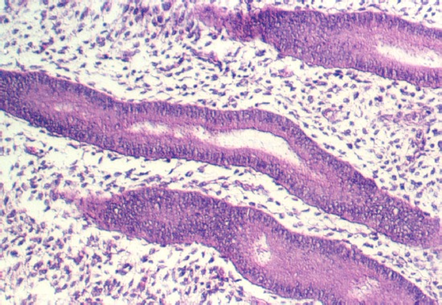

The cervix continues and joins with the vagina. The cervix is lined by simple high columnar epithelium which consists of mucous cells. These are shown in the following views. In the lowest magnification, one can see bundles of smooth muscle in the wall (see below)